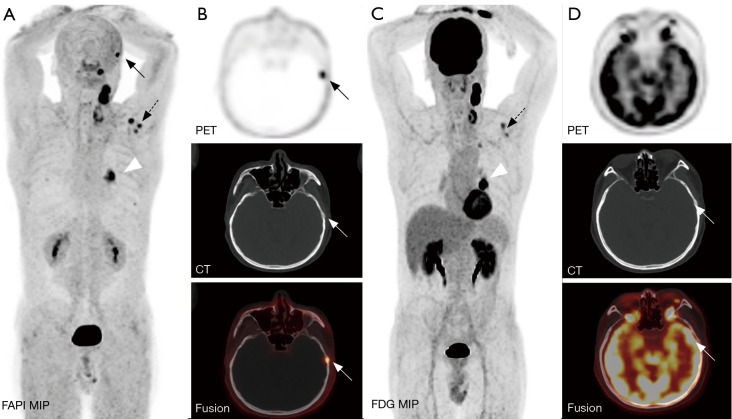

Background: Bone metastases of lung cancer typically indicate disease progression and poor prognosis. Early and accurate detection is crucial for staging, treatment planning, and prognostic evaluation. This study aimed to compare the diagnostic value of gallium 68-labeled fibroblast-activation protein inhibitor-04 ([68Ga]Ga-FAPI-04) and fluorine 18-labeled fluorodeoxyglucose ([18F]FDG) positron-emission tomography/computed tomography (PET/CT) imaging in detecting bone metastases in lung cancer.

Methods: A retrospective analysis was conducted on patients with pathologically confirmed lung cancer and clinically suspected bone metastases. These patients underwent both [68Ga]Ga-FAPI-04 and [18F]FDG PET/CT imaging. Initially, all patient images were visually evaluated, and the diagnostic efficacy of the two imaging methods was compared at both the patient and lesion levels for detecting bone metastases from lung cancer. Additionally, a semi-quantitative analysis was performed to compare the optimal maximum standardized uptake value (SUVmax) threshold and diagnostic efficacy of the two examinations for diagnosing benign and malignant bone lesions.

Results: A total of 25 lung cancer patients were included in the study, with nine confirmed cases and 133 lesions of bone metastases. At the patient level, there were no statistically significant differences in the detection rate, sensitivity, specificity, positive predictive value, negative predictive value, or accuracy between [68Ga]Ga-FAPI-04 and [18F]FDG PET/CT for identifying patients with bone metastases (P>0.05). At the lesion level, the detection rate, sensitivity, negative predictive value, and accuracy of [68Ga]Ga-FAPI-04 PET/CT for detecting bone metastases were higher than those of [18F]FDG PET/CT (81.37% vs. 57.14%, 98.50% vs. 69.17%, 88.24% vs. 34.92%, 90.68% vs. 70.81%), with statistically significant differences (P<0.01). The SUVmax of malignant bone lesions on both [68Ga]Ga-FAPI-04 and [18F]FDG PET/CT was significantly higher than those of benign bone lesions, with statistically significant differences (P<0.05). Moreover, the SUVmax of benign and malignant bone lesions on [68Ga]Ga-FAPI-04 PET/CT was significantly higher than those on [18F]FDG PET/CT, with statistically significant differences (P<0.01). In [68Ga]Ga-FAPI-04 and [18F]FDG PET/CT imaging, the area under the curves (AUCs) of SUVmax for diagnosing bone metastases were 0.856 and 0.724, respectively, with statistically significant differences (P<0.05); the optimal diagnostic thresholds were 5.38 and 3.77, respectively. The sensitivity, negative predictive value, and accuracy of SUVmax based on [68Ga]Ga-FAPI-04 PET/CT for diagnosing lung cancer bone metastases were higher than those based on [18F]FDG PET/CT (80.45% vs. 65.26%, 46.49% vs. 23.26%, 81.25% vs. 67.29%), with statistically significant differences (P<0.05).

Conclusions: Compared to [18F]FDG PET/CT, [68Ga]Ga-FAPI-04 PET/CT significantly improves the detection rate of lung cancer bone metastases at the lesion level. Additionally, [68Ga]Ga-FAPI-04 PET/CT offers superior image contrast and higher SUVmax, which also contribute to improving the accuracy of lung cancer bone metastasis diagnosis. This allows for more accurate staging of patients, enabling precise individualized treatment and improving patient prognosis.